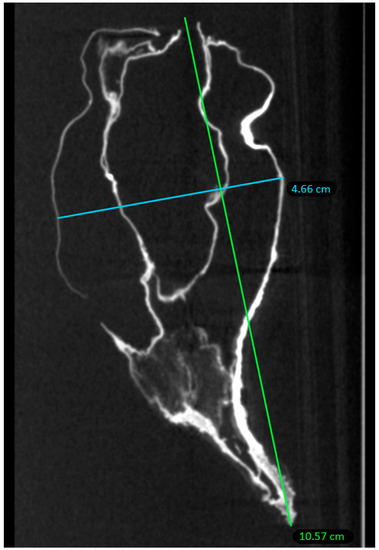

2.2. Micro-CT Scan